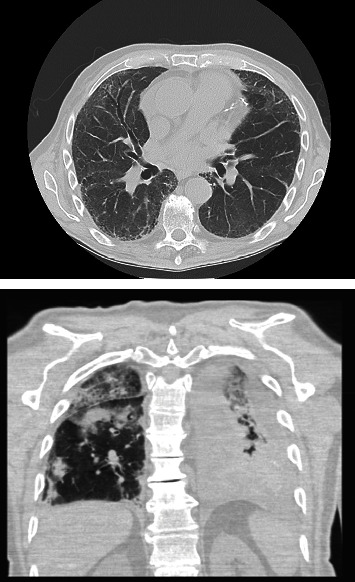

Antineutrophil cytoplasmic antibody (ANCA)-associated vasculitis is a group of rare autoimmune disorders associated with the presence of ANCA autoantibodies. We present the first reported case of acute ANCA-associated vasculitis following coronary artery bypass grafting in a 74-year-old male presenting on postoperative day 13 with shortness of breath, orthopnea, and acute kidney injury. Renal biopsy ultimately showed focal necrotizing and crescentic glomerulonephritis, and the patient was successfully managed with corticosteroids and outpatient rituximab. This rare case highlights the importance of having an expanded differential for uncommon causes of cardiovascular disease and unexpected outcomes after coronary artery bypass grafting.